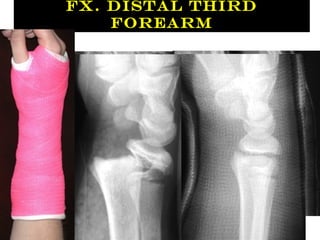

Fx. Distal Third

Forearm